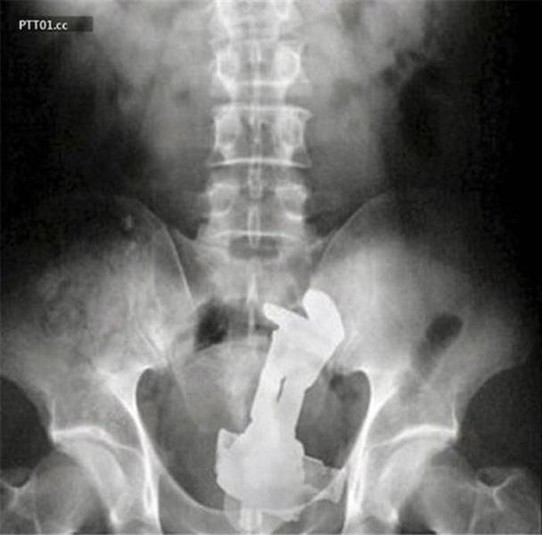

Предметы, которые не очень хочется видеть внутри себя

Под рентгеновскими лучами порой видны не только внутренние органы и кости, но и инородные тела, попавшие в организм

Истории попадания этих предметов в организм могут быть самыми невероятными и запутанными, но больше всего медиков интересует процесс их извлечения, впрочем, в этом заинтересованы и сами пациенты, допустившие нечто подобное со своим телом.